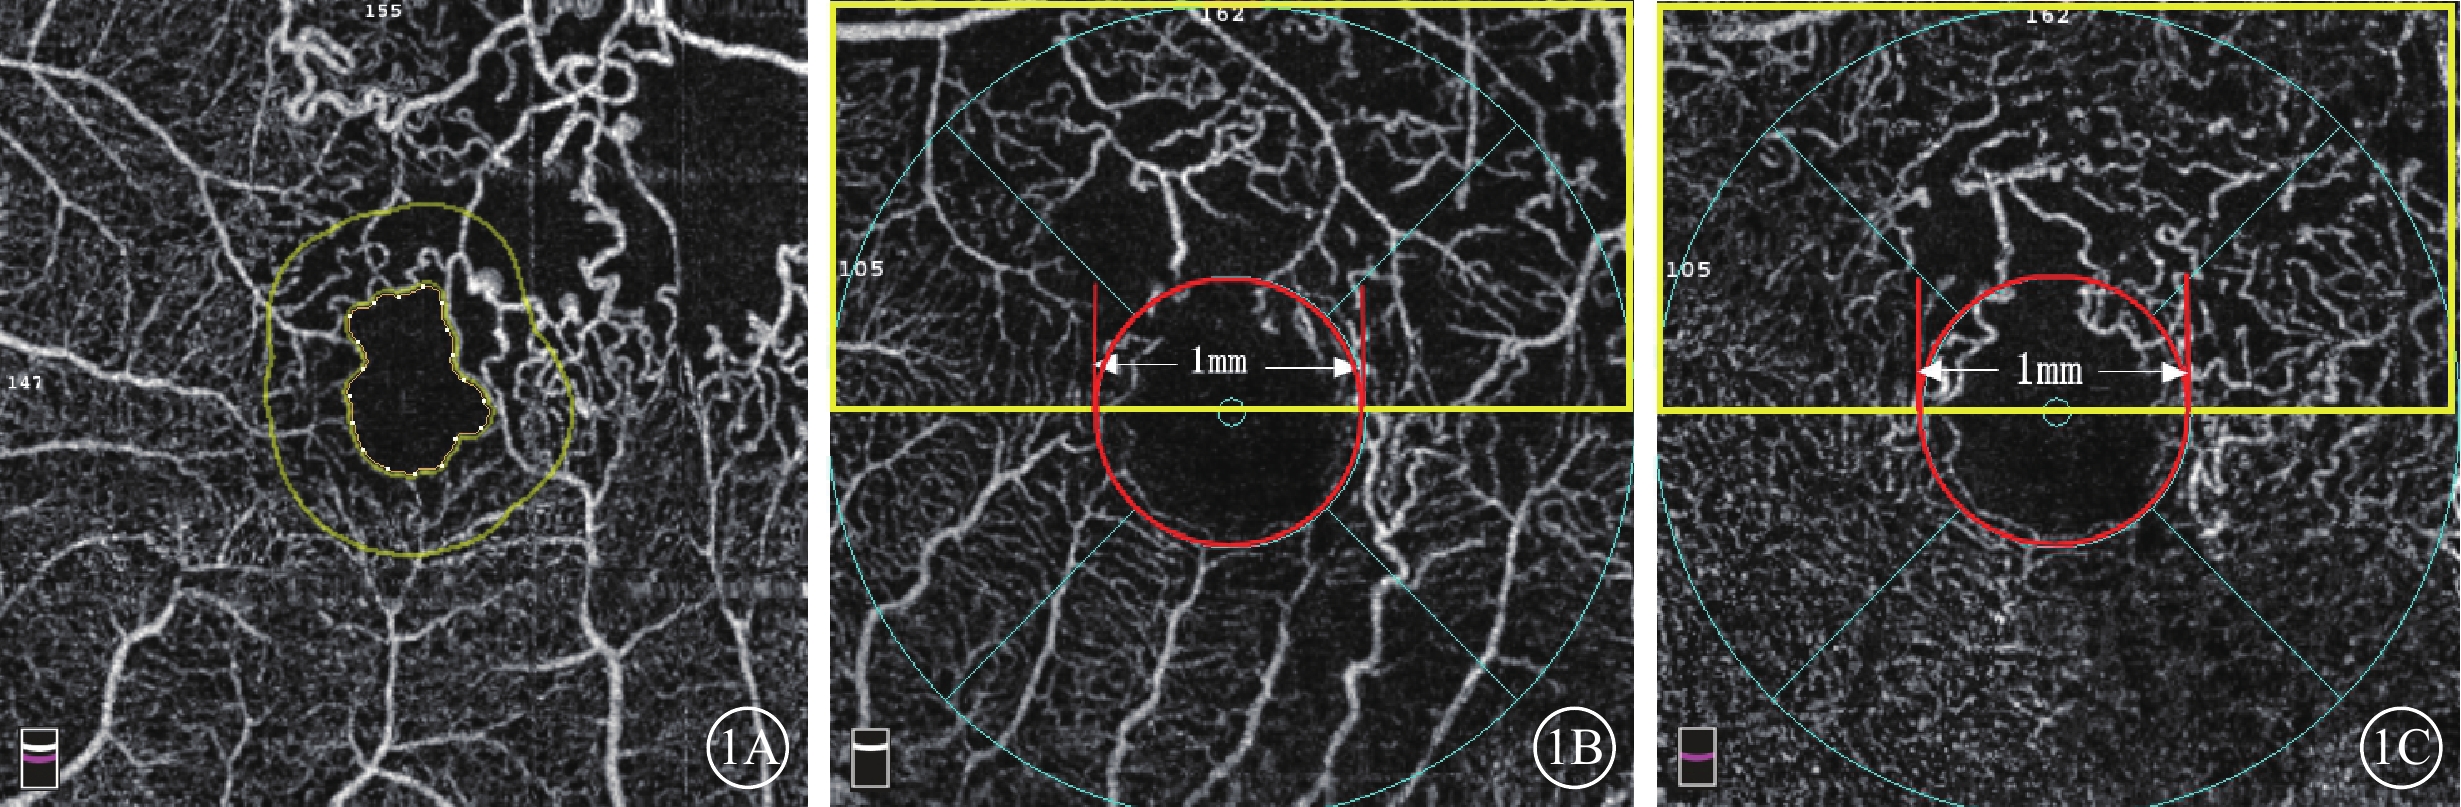

采用美國Optovue公司RTVue-XR Avanti OCT儀行黃斑區OCTA檢查。檢查由同一位熟練醫生獨立操作完成。掃描程序AngioVue Retina,掃描范圍3 mm×3 mm,A掃描為70 000次/s,光源波長840 nm,頻寬50 nm。每次A掃描包含304×304條B掃描線。所采集數據采用系統自帶軟件進行分析,并自動合成4張不同層面OCTA圖像,即SCP、DCP、外層視網膜及脈絡膜毛細血管層。采用設備自帶軟件(OCTA血流量化標準2.0版)測量并計算全層視網膜FAZ面積、PERIM、非圓度指數(AI)以及FAZ范圍300 μm寬度內的血流密度(FD-300)(圖1A),中心凹視網膜厚度(CRT),中心凹SCP視網膜血流密度(SFVD)、中心凹DCP視網膜血流密度(DFVD),BRVO病灶所在區域SCP半側視網膜血流密度(SHVD)、DCP半側視網膜血流密度(DHVD)(圖1B,1C)。SCP為內界膜(ILM)上3 μm至內叢狀層(IPL)下15 μm,包含視神經纖維層和節細胞層;DCP為IPL下15~70 μm,主要包含內核層。全層視網膜是從ILM至內叢狀層邊界之間的視網膜各層;水腫腔位于ILM與IPL之間導致斷面分層發生錯誤時,給予手動調整并記錄調整后的數據。AI=PERIM/等面積標準圓周長。75只眼中,28只眼(37.33%)FAZ面積自動識別區域與FAZ真正呈現區域不符,給予手動調整并記錄(圖2)。

圖1

FAZ面積、FERIM、FD-300、黃斑區血流密度測量示意圖。1A示FAZ面積(內圈不規則黃色線內區域)、FERIM(內圈不規則黃色線周長)、FD-300(黃色線內外圈之間環形區域);1B、1C分別示SCP、DCP.SFVD(紅色線圈內區域),SHVD(黃色方框內)

圖1

FAZ面積、FERIM、FD-300、黃斑區血流密度測量示意圖。1A示FAZ面積(內圈不規則黃色線內區域)、FERIM(內圈不規則黃色線周長)、FD-300(黃色線內外圈之間環形區域);1B、1C分別示SCP、DCP.SFVD(紅色線圈內區域),SHVD(黃色方框內)

采用美國Optovue公司RTVue-XR Avanti OCT儀行黃斑區OCTA檢查。檢查由同一位熟練醫生獨立操作完成。掃描程序AngioVue Retina,掃描范圍3 mm×3 mm,A掃描為70 000次/s,光源波長840 nm,頻寬50 nm。每次A掃描包含304×304條B掃描線。所采集數據采用系統自帶軟件進行分析,并自動合成4張不同層面OCTA圖像,即SCP、DCP、外層視網膜及脈絡膜毛細血管層。采用設備自帶軟件(OCTA血流量化標準2.0版)測量并計算全層視網膜FAZ面積、PERIM、非圓度指數(AI)以及FAZ范圍300 μm寬度內的血流密度(FD-300)(圖1A),中心凹視網膜厚度(CRT),中心凹SCP視網膜血流密度(SFVD)、中心凹DCP視網膜血流密度(DFVD),BRVO病灶所在區域SCP半側視網膜血流密度(SHVD)、DCP半側視網膜血流密度(DHVD)(圖1B,1C)。SCP為內界膜(ILM)上3 μm至內叢狀層(IPL)下15 μm,包含視神經纖維層和節細胞層;DCP為IPL下15~70 μm,主要包含內核層。全層視網膜是從ILM至內叢狀層邊界之間的視網膜各層;水腫腔位于ILM與IPL之間導致斷面分層發生錯誤時,給予手動調整并記錄調整后的數據。AI=PERIM/等面積標準圓周長。75只眼中,28只眼(37.33%)FAZ面積自動識別區域與FAZ真正呈現區域不符,給予手動調整并記錄(圖2)。

圖1

FAZ面積、FERIM、FD-300、黃斑區血流密度測量示意圖。1A示FAZ面積(內圈不規則黃色線內區域)、FERIM(內圈不規則黃色線周長)、FD-300(黃色線內外圈之間環形區域);1B、1C分別示SCP、DCP.SFVD(紅色線圈內區域),SHVD(黃色方框內)

圖1

FAZ面積、FERIM、FD-300、黃斑區血流密度測量示意圖。1A示FAZ面積(內圈不規則黃色線內區域)、FERIM(內圈不規則黃色線周長)、FD-300(黃色線內外圈之間環形區域);1B、1C分別示SCP、DCP.SFVD(紅色線圈內區域),SHVD(黃色方框內)